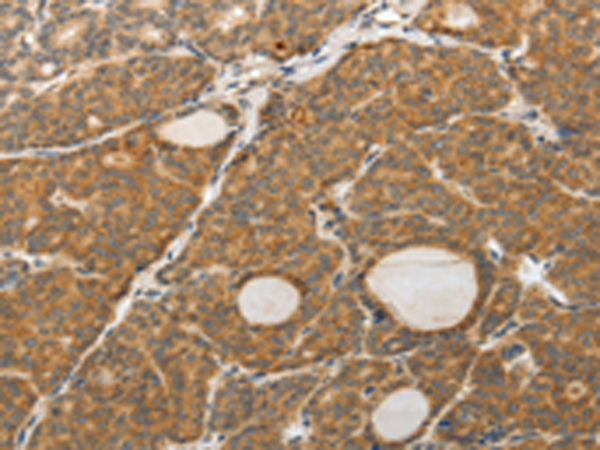

分类: 科研抗体货号: P11178别名: AR; ADR; ALR2; ALDR1应用: WB,IHC反应种属: Human